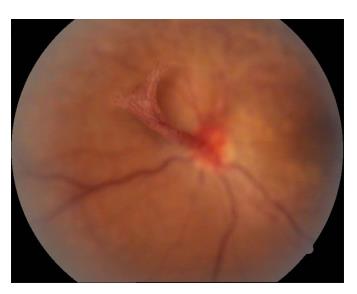

患者女,2 3岁,既往高血压病病史,因“左眼视物模糊1 3天”于2011年4月1 5日就诊于济宁医学院附属医院眼科,眼科查体:右眼视力为0.6,左眼视力为0.08,双眼眼前节情况正常,右眼眼底动脉反光增强,静脉略迂曲(图1),左眼眼底颞上方视网膜大片火焰状出血、棉绒斑、静脉迂曲、黄斑水肿(图2 )。眼底荧光血管造影示:左眼颞上方网膜大片荧光遮蔽,微血管瘤,未见明显无灌注区(图3 ),诊断“左眼视网膜分支静脉阻塞,双眼高血压视网膜病变”,给予随访观察,控制血压。发病36 d时,眼底检查见:左眼视盘新生血管(图4);眼底血管造影检查见:左眼视盘荧光渗漏,颞上视网膜大片无灌注区(图5),给予眼底病变区视网膜激光光凝治疗。发病75 d时,眼底检查见:左眼视盘新生血管增殖膜,颞上方视网膜血管闭塞,散在激光斑(图6,7 ),补充病变区激光治疗。发病103 d时,眼底血管造影检查见:左眼视盘荧光渗漏,颞上方视网膜异常血管网(图8,9 ),补充病变区激光治疗。发病138 d时,左眼视力为0.02,视盘形成新生血管膜,表面血管旺盛(图1 0,11),再次补充病变区激光治疗。1 0年后因“右眼视力下降3天”就诊,查体:右眼视力为0.4,左眼视力为0.4;眼底检查见:左眼视盘新生血管膜机化萎缩,表面无血管(图12),右眼后极部颞下、颞上视网膜棉绒斑,鼻下和鼻侧视网膜浅层出血,鼻上视网膜少许硬性渗出(图13)。

20230106105207_6191.jpg

图2 左眼眼底彩照见颞上方视网膜大片火焰状出血,棉绒斑,静脉迂曲,黄斑水肿(发病13 d)

Figure 2 Color fundus of the left eye showed large flaming hemorrhage, cotton velvet spot, and tortuous veins of the supratemporal retina , macular edema (oneset of 13 d)